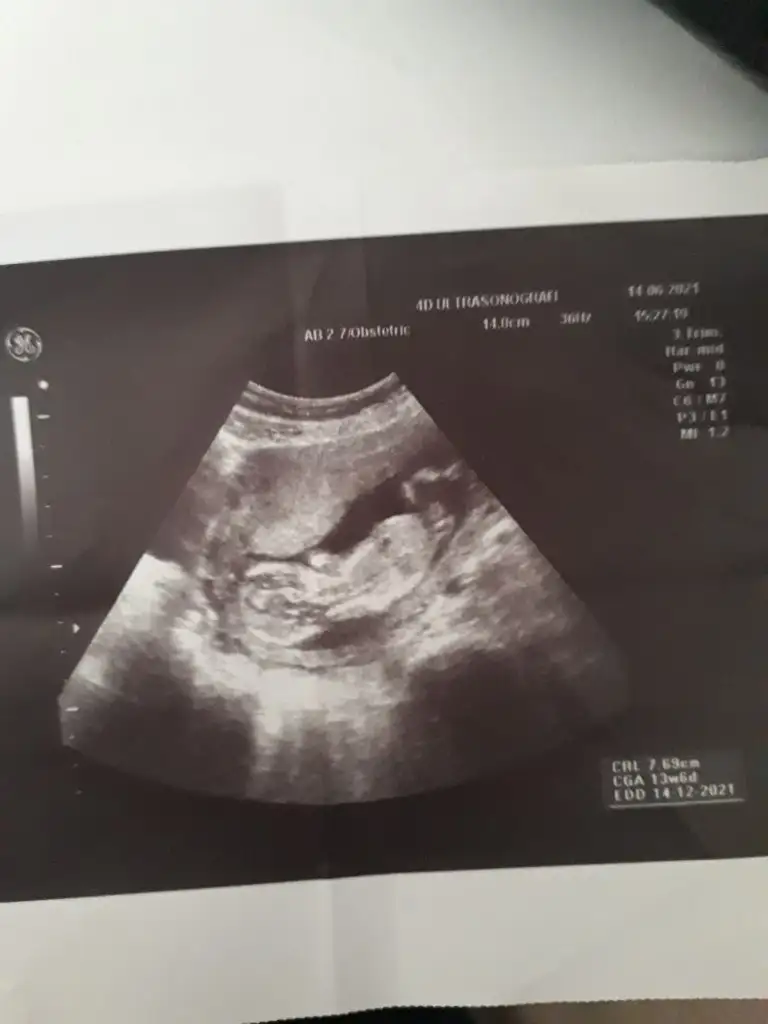

Kız görünüyorIkra meyra 12+4 canm

Tsk ederm canm önceki fotolarda erkek demistin ama sorun yok 1 ay sonra öğrenince oylayacagim anketiniKız görünüyor![]()

Önceki usg kaç haftalık bu kaç haftalik önceki daha net ise erkektir 11 12 13 haftalar olmalıTsk ederm canm önceki fotolarda erkek demistin ama sorun yok 1 ay sonra öğrenince oylayacagim anketini![]()

Ikra meyra gecen sene kizimi tahminde dogru bilmistin canim 13+3haftalik gebeyim tekrardan var mi bi tahminin